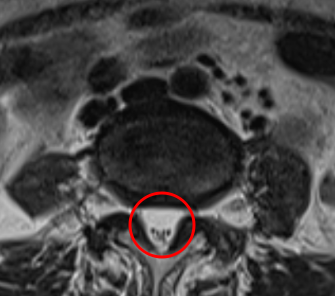

治療前

腰痛MRIを確認したところ、L3/4と、L4/5の2か所に腰椎すべり症が原因とみられる脊柱管狭窄症を認めました。L4/5は特に狭窄が酷くなっていました。

痛みの原因は2か所の狭窄だと考えられます。